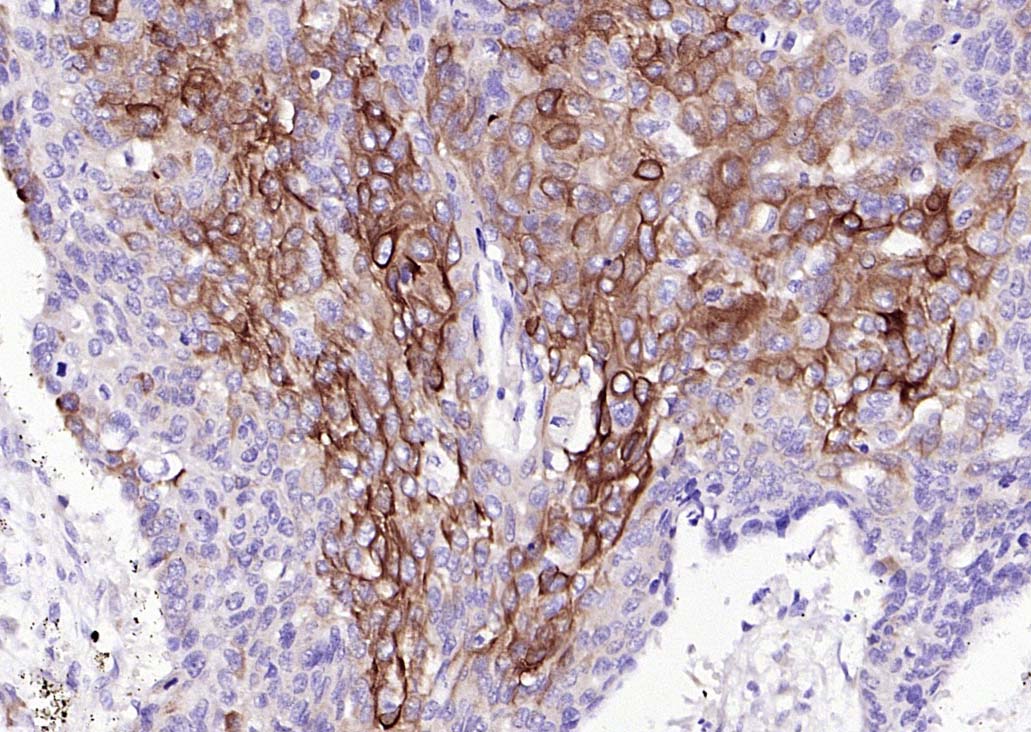

Vimentin is a developmentally regulated intermediate filament protein (IFP) found in cells of mesenchymal origin. It is believed to be involved with the intracellular transport of proteins between the nucleus and plasma membrane. Unlike other IFP proteins, vimentin is expressed, along with desmin, during the early stages of cellular development. During the development process, vimentin is exchanged for new, tissue-specific IFPs. Vimentin has been implicated to be involved in the rate of steroid synthesis via its role as a storage network for steroidogenic cholesterol containing lipid droplets. Vimentin phosphorylation by a protein kinase causes the breakdown of intermediate filaments and activation of an ATP and myosin light chain dependent contractile event. This results in cytoskeletal changes that facilitate the interaction of the lipid droplets within mitochondria, and subsequent transport of cholesterol to the organelles leading to an increase in steroid synthesis.

| IHC-P | Human, Mouse, Rat | 1:100-500 | |